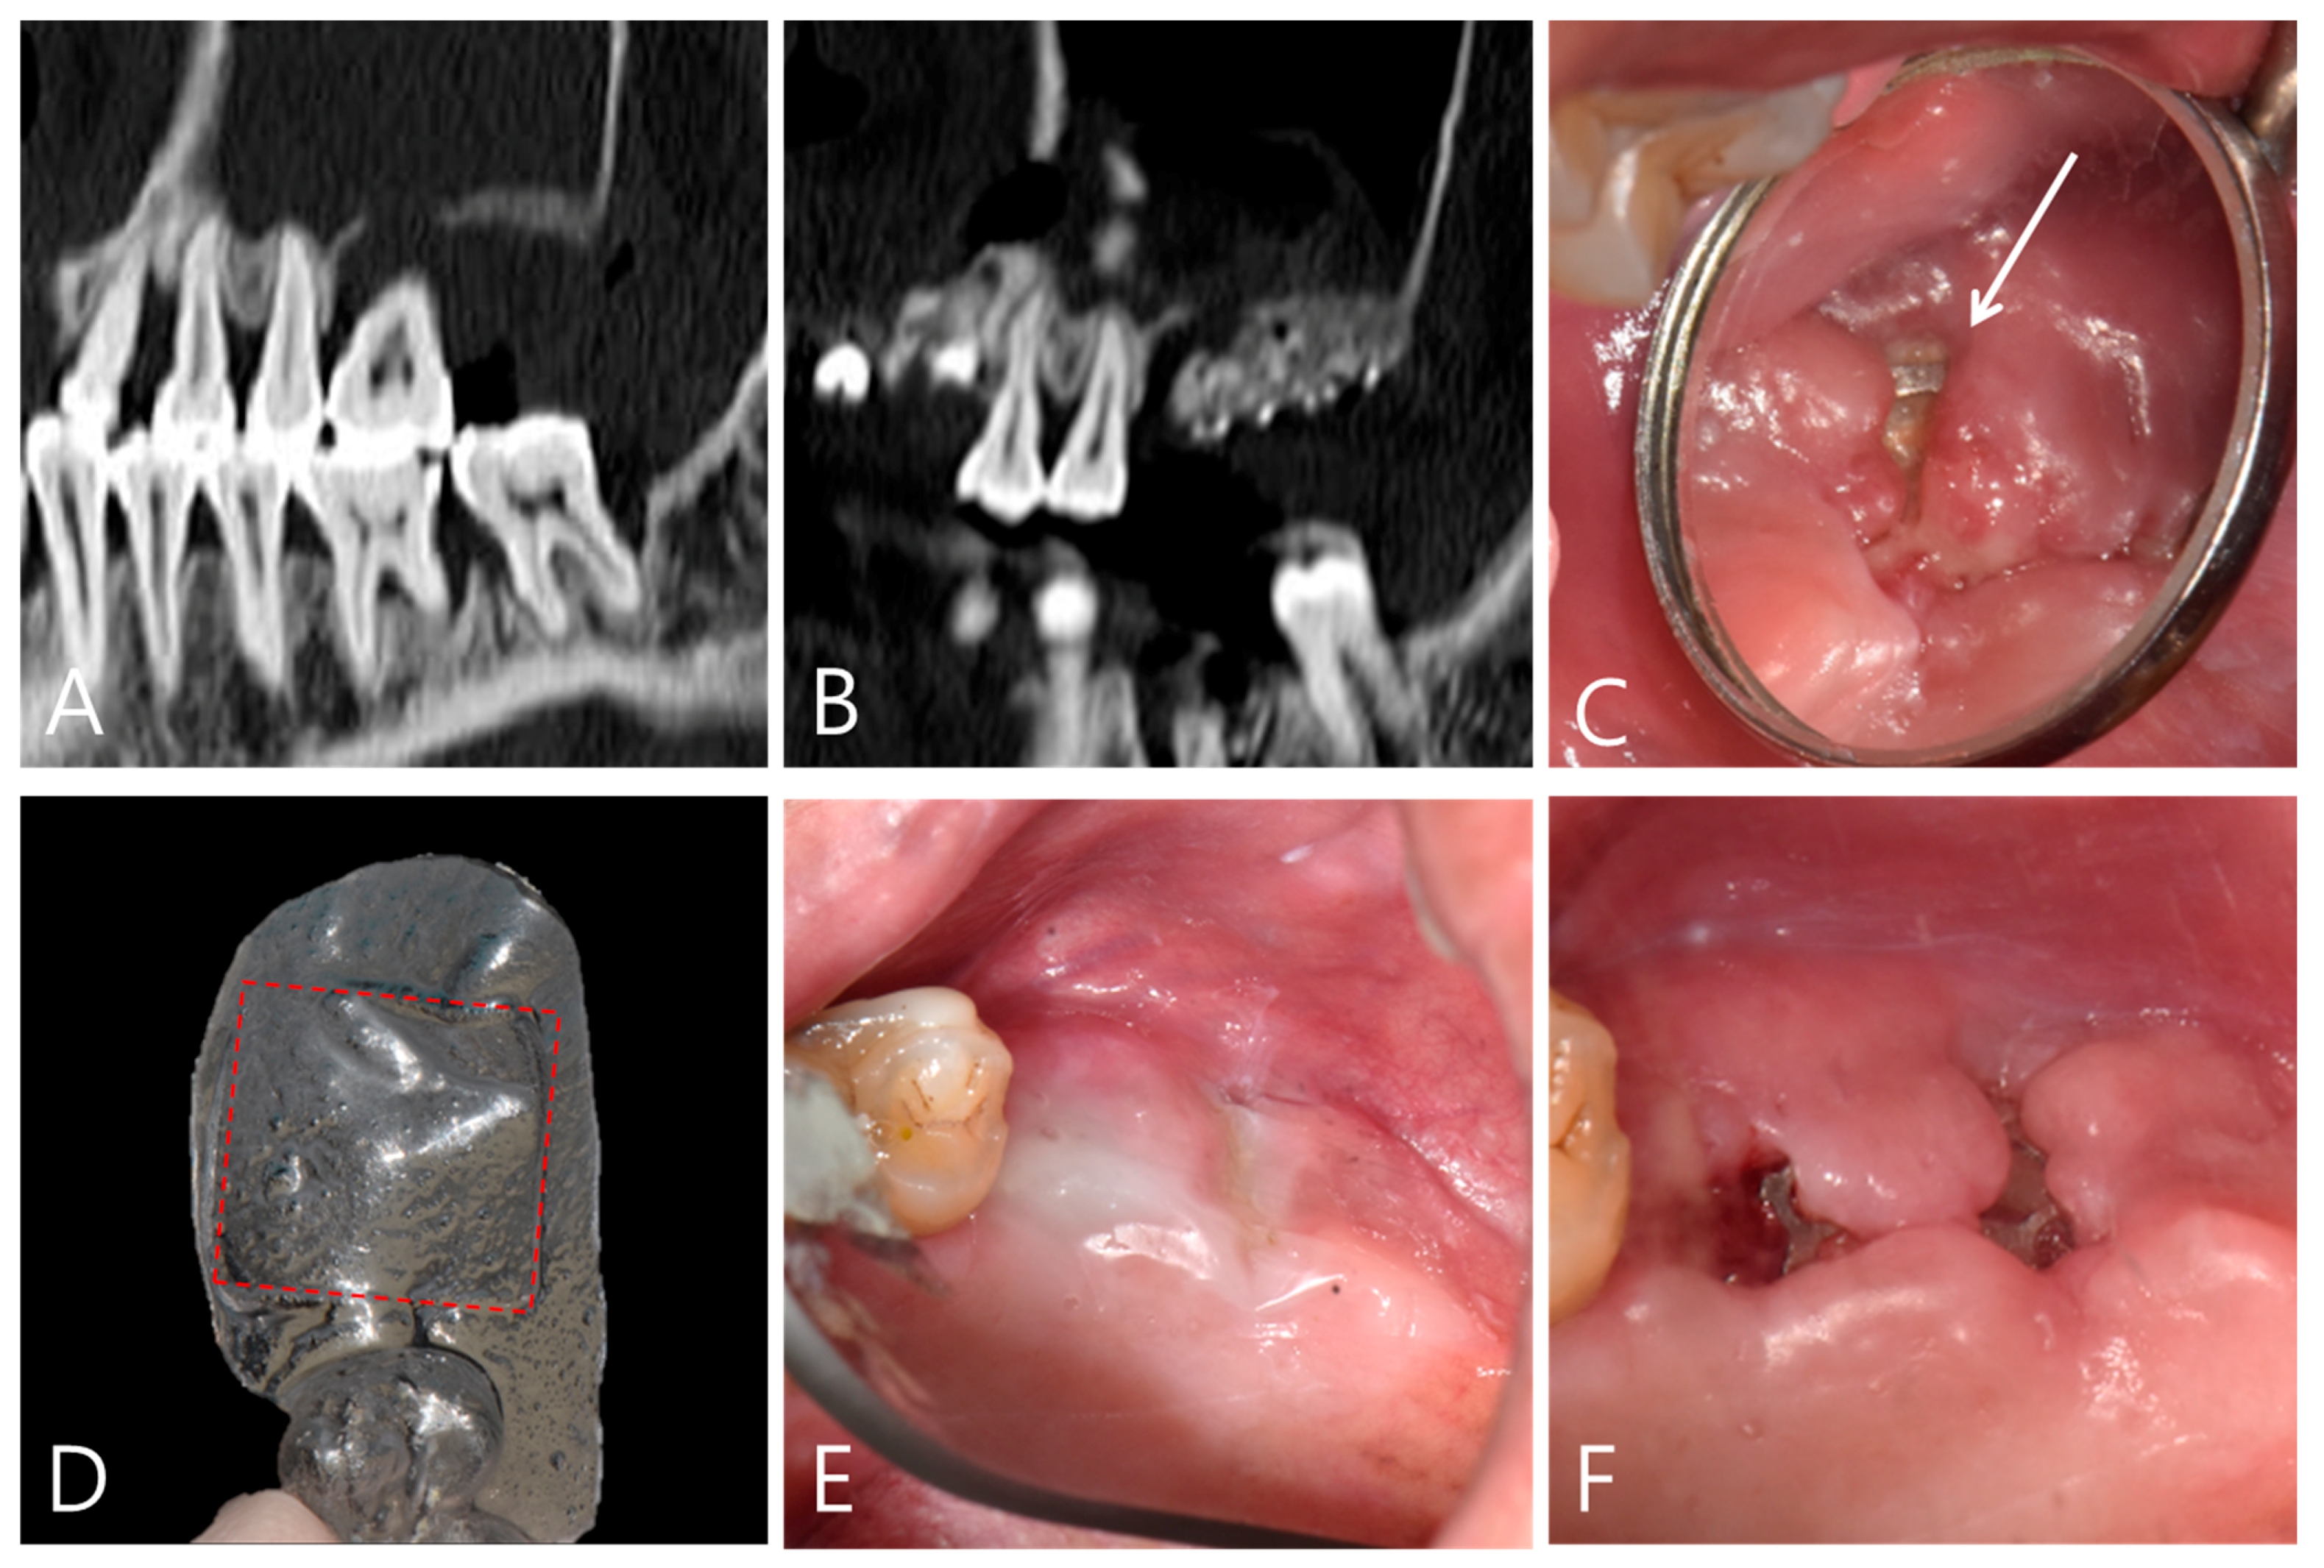

3.2. Case #2. Wound Dehiscence after an Autogenous Bone Graft with a Titanium Mesh and Histology Analysis with Mesh Removal at 10 Weeks Postoperatively